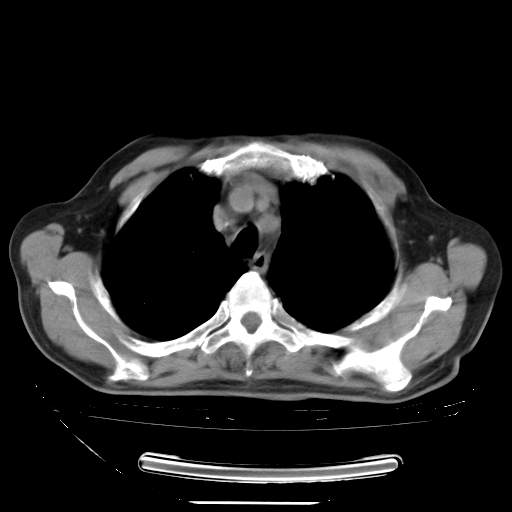

今天复查肺部CT,发现双肺广泛磨玻璃样改变。所以我把3月19日和5月9日相隔50天的肺部CT上传。请大家会诊。

5月9日肺部CT(在4月27日齐鲁医院肺部CT描述部分肺组织磨玻璃样改变,12天后肺组织广泛磨玻璃样改变)

大致读了系列胸部CT:纵隔窗无明显异常,肺窗:从4、27至今:主要是双肺中下野外带可见毛玻璃样改变,目前处于急性肺泡炎阶段,至于原因考虑1、结替组织或胶原血管性疾病所致?2、恶性疾病如恶组在肺部所致的表现或细支气管肺泡癌?3、药物或其它原因如肺蛋白沉着症所致肺泡炎目前不太可能?总之,明天就去请我院的呼吸科、感染科、血液科和临免专家会诊哈。